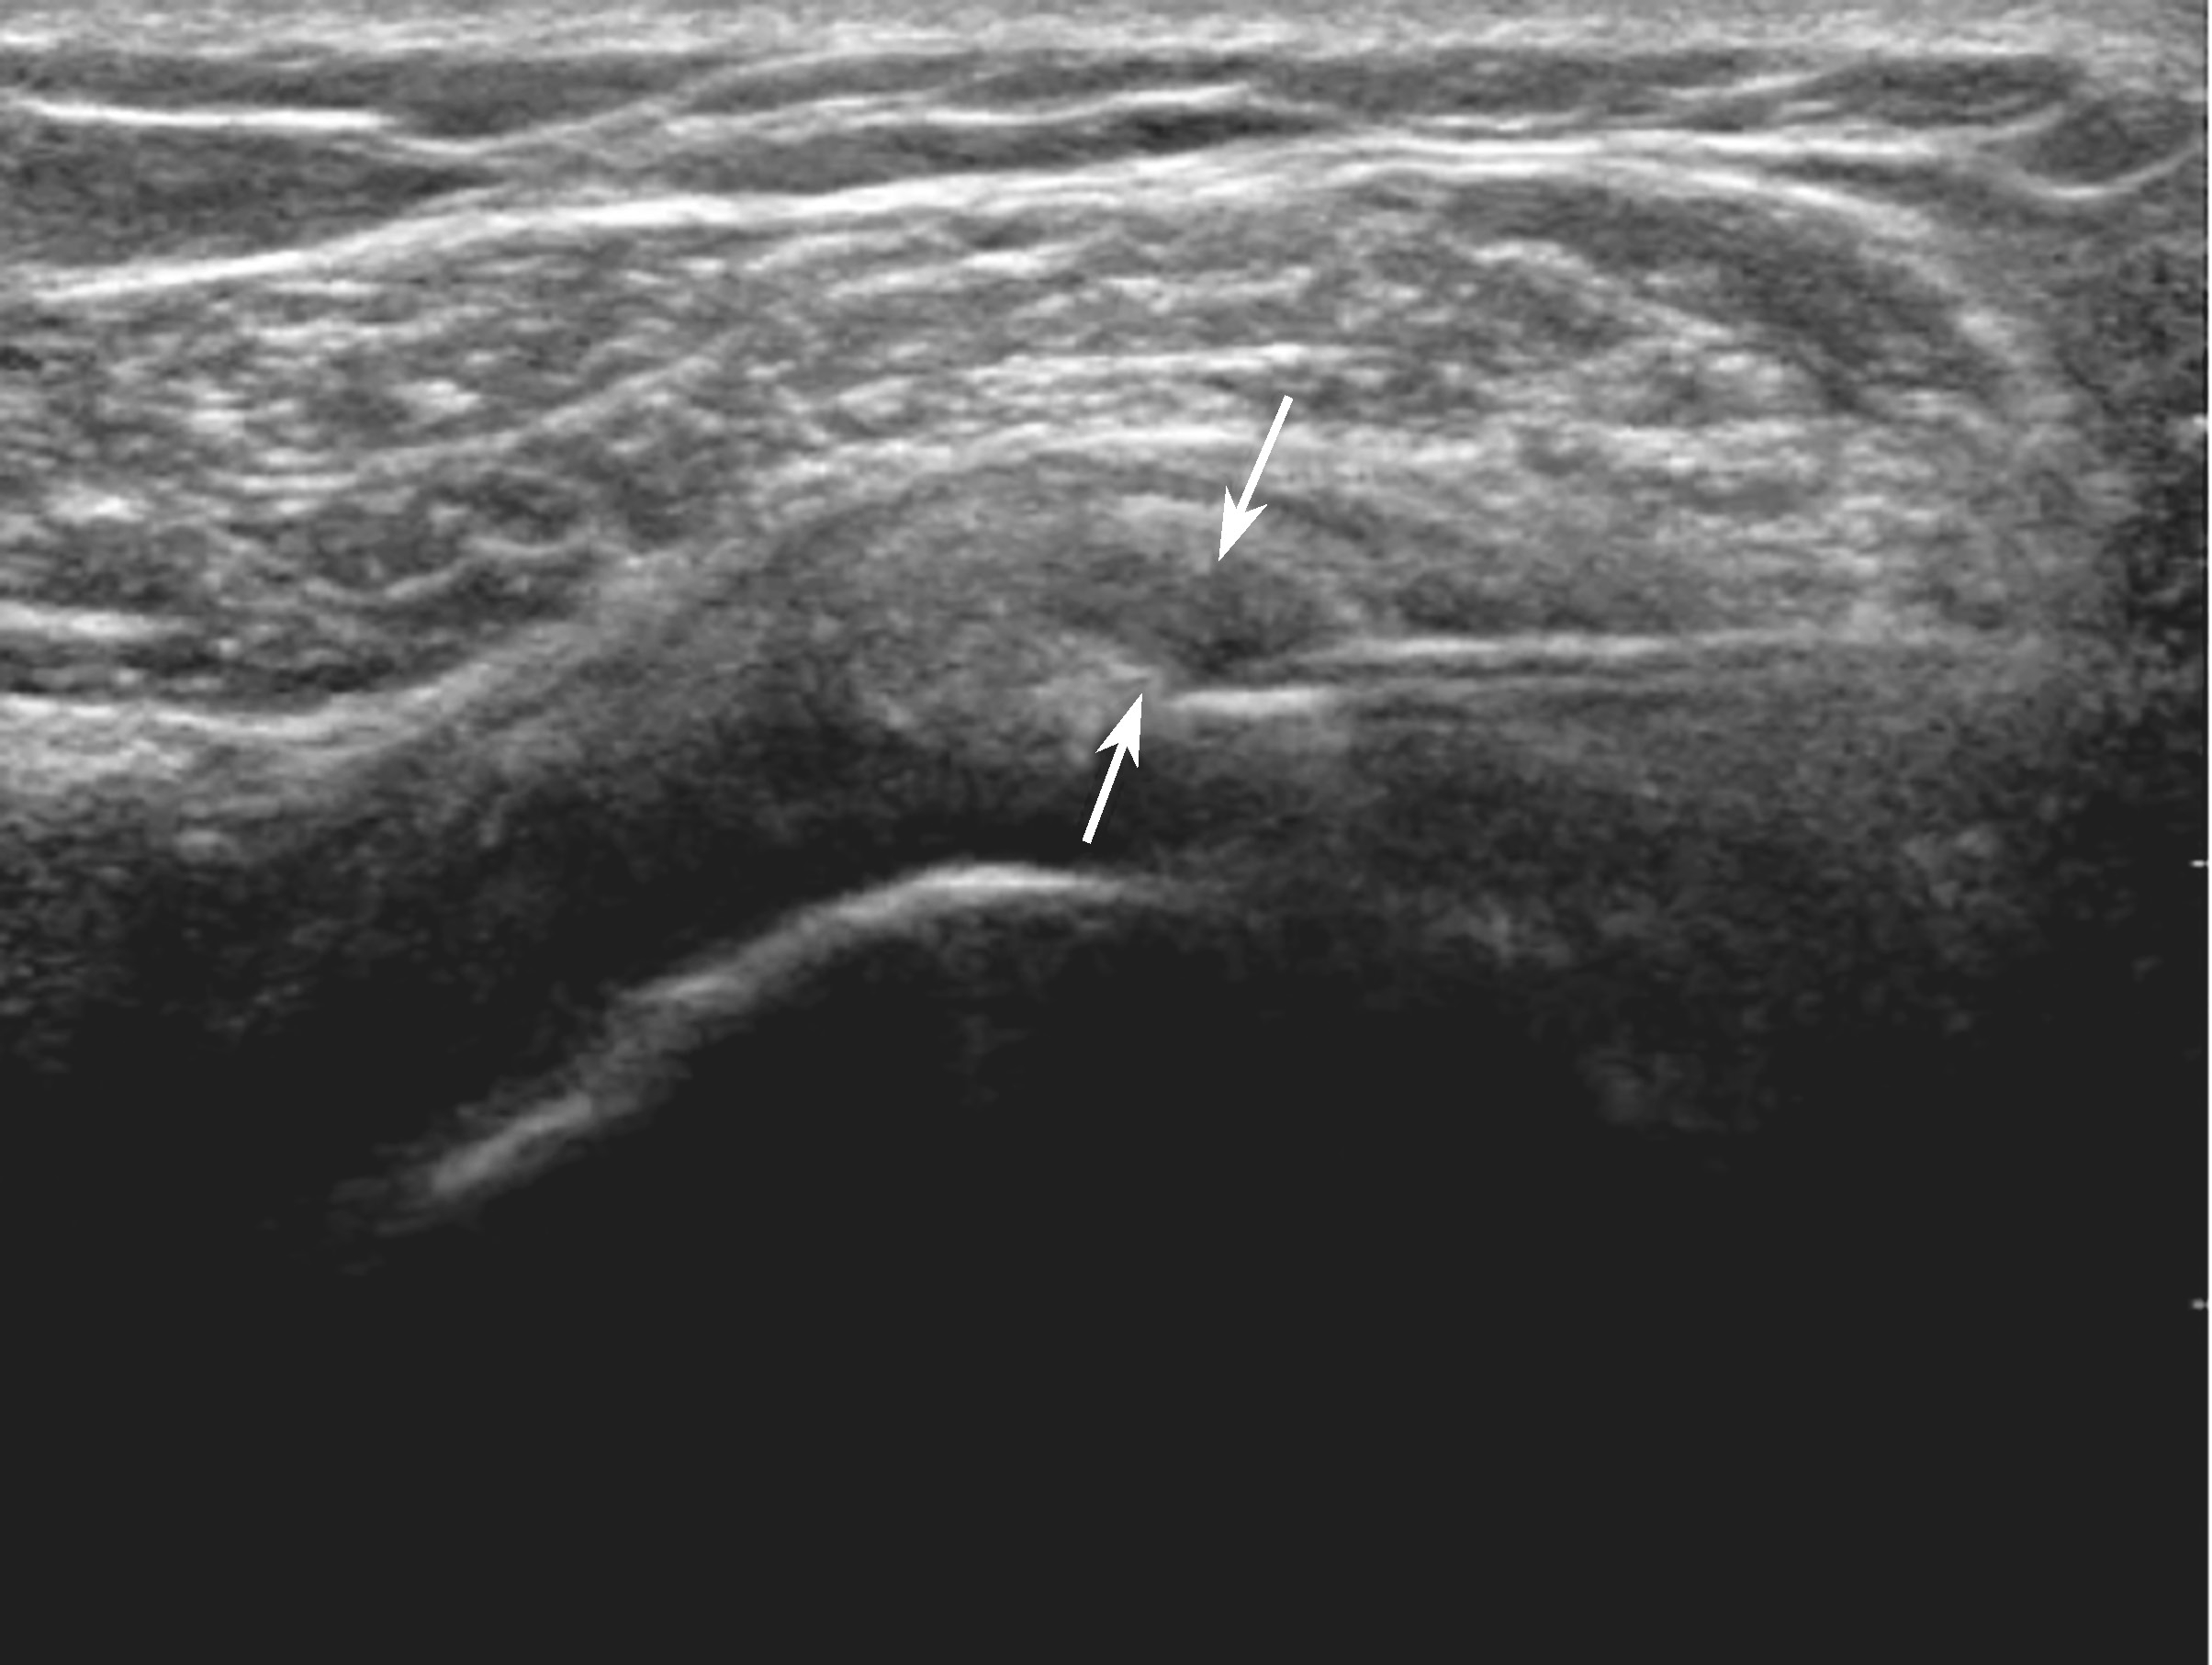

(1)在超声实时监视下(图2-2-3),将穿刺针一次性刺入钙化灶中心部位(图2-2-4),将针管内的生理盐水和利多卡因混合液(比例5∶1)不断推注和抽吸,此时可见钙化灶中心空洞形成(液体回声,图2-2-5),且冲洗过程中呈“鱼嘴”样开闭,由于压力作用可见乳白色物质被吸入注射器内(图 2-2-6)。

▲ 图2-2-5 超声引导下肩袖钙化性肌腱炎介入治疗超声图

箭头:冲洗过程中钙化灶内空洞形成